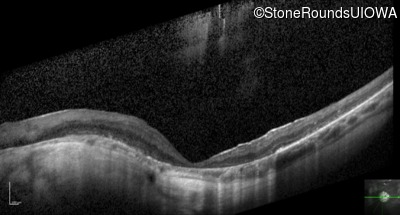

Optical Coherence Tomography - Right - 20/125

Exemplar / OCT Stack

OCT Stack